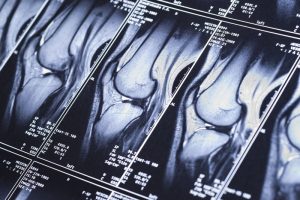

Біль після фізичних навантажень є поширеною причиною звернення до лікаря, особливо серед людей, які регулярно займаються спортом, фітнесом або виконують інтенсивну фізичну роботу. Після тренувань дискомфорт може виникати як у професійних спортсменів, так і у новачків, які різко збільшили навантаження або порушили техніку виконання вправ. У частині випадків біль є нормальною фізіологічною реакцією організму, однак нерідко він сигналізує про ушкодження м’яких тканин. МРТ у медичному центрі «Юнімед» дозволяє точно визначити причину больового синдрому та оцінити стан м’язів і сухожиль без променевого навантаження, що є важливим для безпечного повернення до фізичної активності.

Такі ушкодження не завжди можна визначити під час зовнішнього огляду, проте вони чітко візуалізуються при магнітно-резонансній томографії.